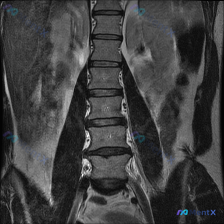

有人看了一张腰椎MRI T2序列冠状位的图,第一反应是「脊柱侧弯(Scoliosis)」,但仔细读片后发现结论完全不一样。

先放核心影像表现:

- 脊柱对线:腰椎序列基本连续,未见明显的侧弯或滑脱征象,椎体边缘清晰,无明显骨质破坏

- 椎间盘:下腰椎(L4/L5、L5/S1)椎间隙明显变窄,T2信号显著减低(黑盘征)

- 小关节:双侧小关节面有骨质增生,信号不均

- 神经根/椎管:L4/L5、L5/S1水平椎间孔区域有占位效应,神经根周围脑脊液高信号带变窄

- 椎旁肌:双侧对称,信号无异常